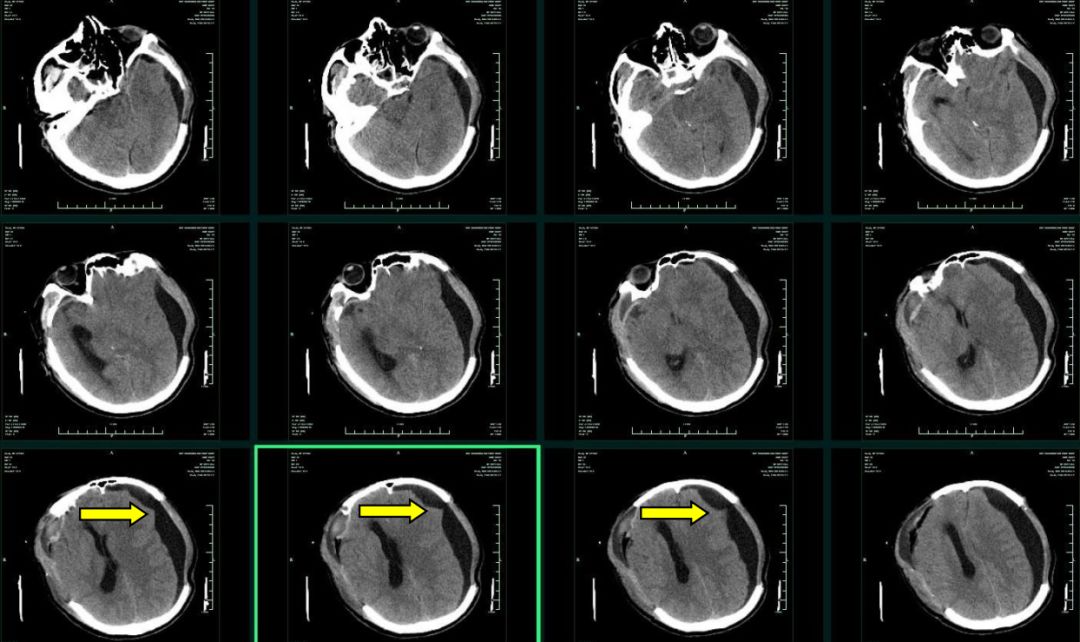

鉴于上述情况,科室讨论决定行手术探查。逐在全麻下行颅骨缺损修补+硬膜下腔探查。术中见额部硬脑膜悬吊处有蛛网膜缝住,并与硬脑膜一起悬吊,蛛网膜呈“帐篷”样隆起,将“帐篷”样隆起的蛛网膜悬吊线剪断(图6), 蛛网膜悬吊处有脑脊液流出,双极电凝电灼蛛网膜悬吊处。重新缝合硬脑膜,并行颅骨修补术(图7)。

图6. 左额部切开硬脑膜探查,见蛛网膜被悬吊,与硬脑膜悬吊线对应。拆除缝线,松解蛛网膜,脑组织未能迅速复位,可见脑脊液从蛛网膜悬吊处流出。双极电凝蛛网膜悬吊处,松解之。